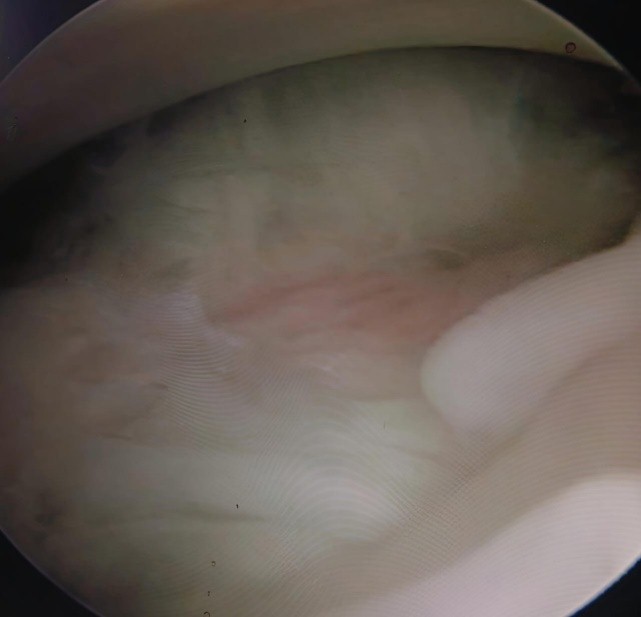

Patients in the ACR group were similarly induced with short-duration GA and positioned supine. Diagnostic arthroscopy was performed via a posterior portal to avoid cartilage injury. Under direct visualization, a 360° circumferential release was performed by sequentially releasing the rotator interval, coracohumeral ligament, and middle glenohumeral ligament, followed by release of the anterior, posterior, and inferior capsules (Figs. 3 and 4). Early mobilization exercises were initiated within 24 h postoperatively (Fig. 5).

Figure 4: Fibrotic bridging across the anterior capsule in refractory frozen shoulder.

Figure 5: Posterior capsule after partial release in refractory frozen shoulder.